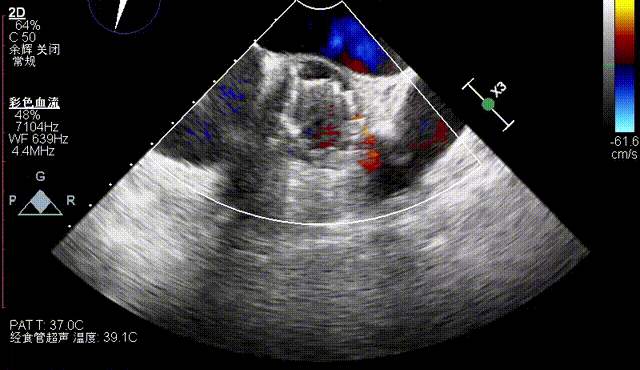

术后即刻评估

术后即刻TEE示主动面瓣膜最大峰值血流速为1.1m/s,平均跨瓣压差为2mmHg,少量瓣周漏。

术后即刻TEE示主动脉瓣膜最大峰值血流速为2.4m/s,平均跨瓣压差为11mmHg,支架内未见明显反流或瓣周漏。

术后即刻TEE示主动面瓣膜最大峰值血流速为2.1 m/s,平均跨瓣压差为8.6 mmHg,少量瓣周漏。